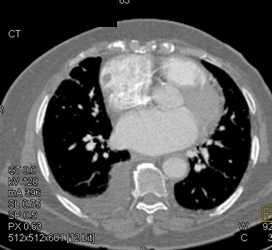

Diagnosis

Diseased LAD